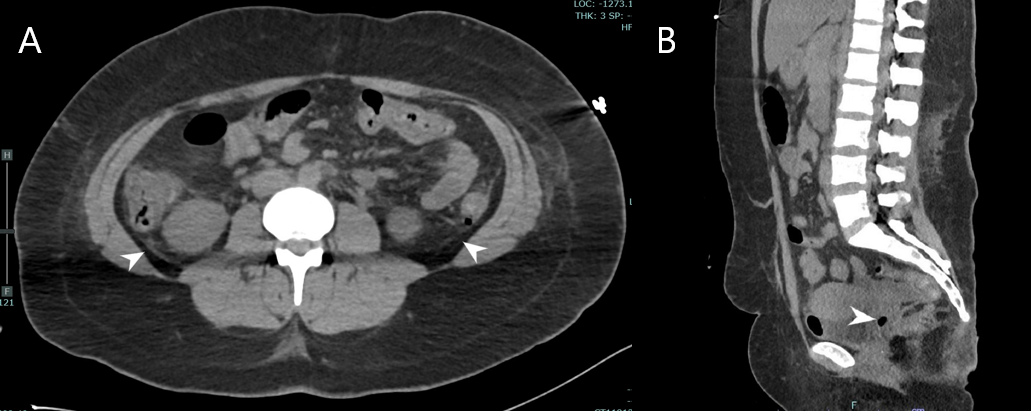

Case Presentation: Patient was a 26-year-old female with history of methamphetamine abuse, previous C trachomatis infection, and heart failure with reduced ejection fraction who presented via EMS for acute hypoxic respiratory failure and unresponsiveness and was intubated in ED. Initial vitals include systolic blood pressure of 80, undetectable diastolic blood pressure, heart rate of 168 beats per minute, respiratory rate of 31 breaths per minute, temperature of 40.9 °C, and oxygen saturation of 96% on the ventilator. Exam was significant for sinus tachycardia, lungs clear to auscultation, soft abdomen, and petechiae on bilateral upper extremities. Lab abnormalities included creatinine of 2.35 mg/dL, bicarbonate of 13 mmol/L, AST 65 U/L, and ALT 78 U/L. Toxicology screen was positive for methamphetamine. IV norepinephrine, meropenem, and vancomycin were initiated. On day two of admission, the patient developed DIC with mucosal bleeding, decreased platelets, decreased fibrinogen, elevated INR, and elevated D-Dimer. Blood, urine, and respiratory cultures grew no organisms. On day four of admission, nursing staff noticed foul-smelling, purulent vaginal discharge. CT of the abdomen-pelvis found intra-abdominal free fluid and intrauterine free air (Figure 1).Vaginal wet preparation microscopy revealed T vaginalis. Lab testing for C trachomatis, N Gonorrhoeae, and M Genitalium were negative. Rapid plasma reagin and HIV testing were negative. Antibiotics were adjusted to doxycycline, metronidazole, and cefepime. The patient’s hemodynamic instability improved and her DIC resolved. She was extubated on day 7 of hospital admission and discharged without further complication.